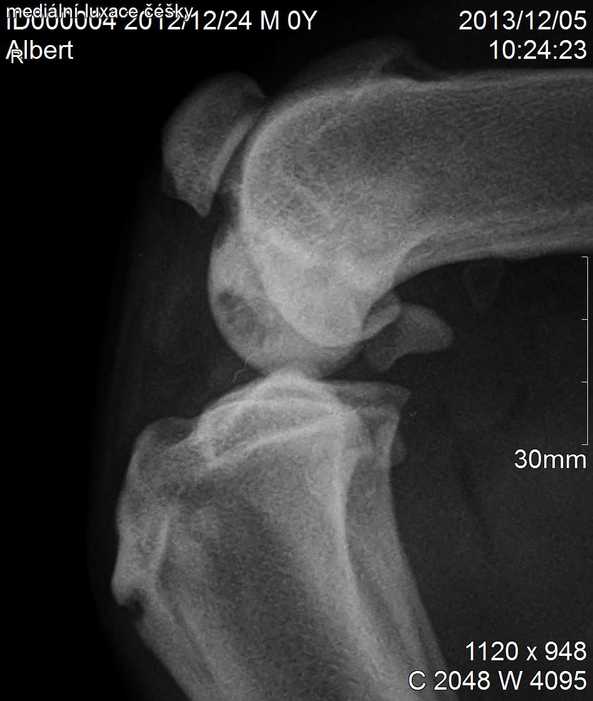

Úvod > Galerie > RTG snímky